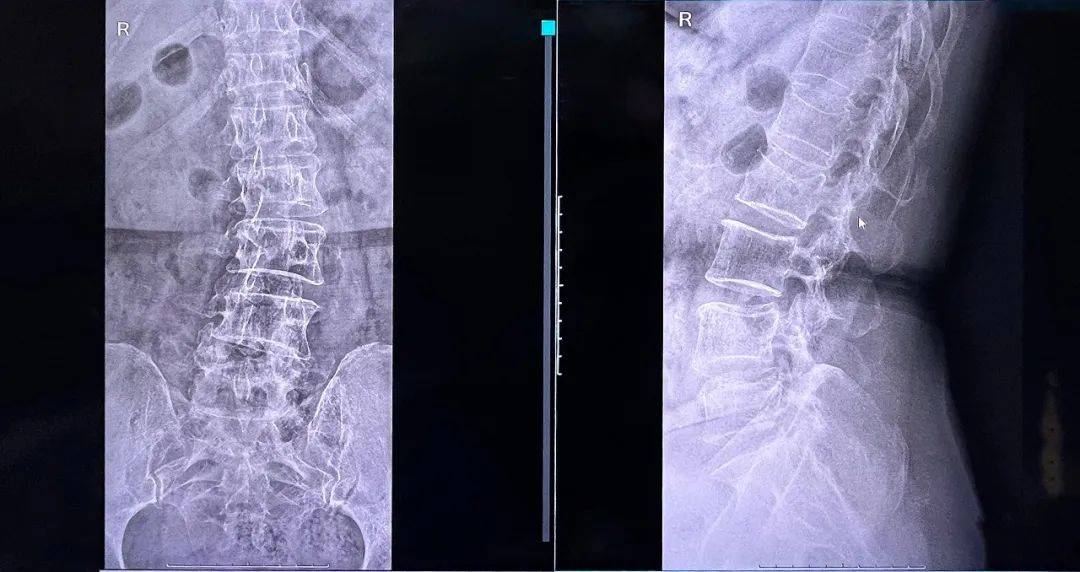

骨水泥在椎體內的彌散效果良好,注入量充足、無滲漏。整體手術時間縮短,讓患者在本院獲得好的治療。